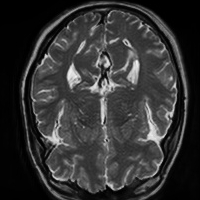

4.4 Qualitative Evaluation

In Figure 5 we analyze the prediction quality of our and compared approaches in a qualitative way. Considering modality propagation in MRI, we see that usage of uncertainty-aware patch invariance (UAPI) gives a better detailed weighting of the cerebrospinal fluid in the middle of the brain. In general, employing patch invariance yields better preservation of fine structures. This observation also applies to accelerated MRI enhancement. In particular, CUT and UAPI provide comparatively sharper knee images with more high-frequency details than the other methods.